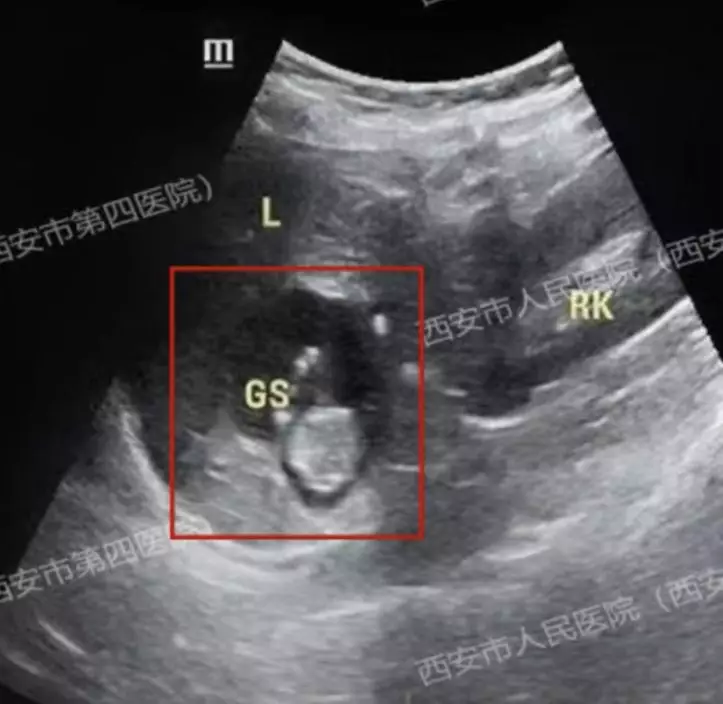

停經就醫揭孕囊出現在肝臟表面

早前,陝西西安一名40歲女子王女士(化名)因停經50日到醫院求診,經抽血檢測後證實已懷孕。然而,進一步超聲波檢查卻未能在子宮及輸卵管周邊發現孕囊。醫療團隊經過持續追查發現,孕囊竟然出現在王女士的肝臟表面,屬於極為罕見的「肝臟妊娠」,是一種高危又罕見的宮外孕類型之一。

胚胎侵蝕肝血管 風險較宮內妊娠高出約90倍

福建省人民醫院專家指出,肝臟妊娠是指胚胎附著於肝臟表層,隨著胎兒生長,會逐漸侵蝕肝內血管,一旦發生破裂,極有可能引致短時間內大量出血,甚至危及性命。此類個案的孕婦病死率遠高於一般妊娠,據稱可較宮內妊娠高出約90倍,風險極高。